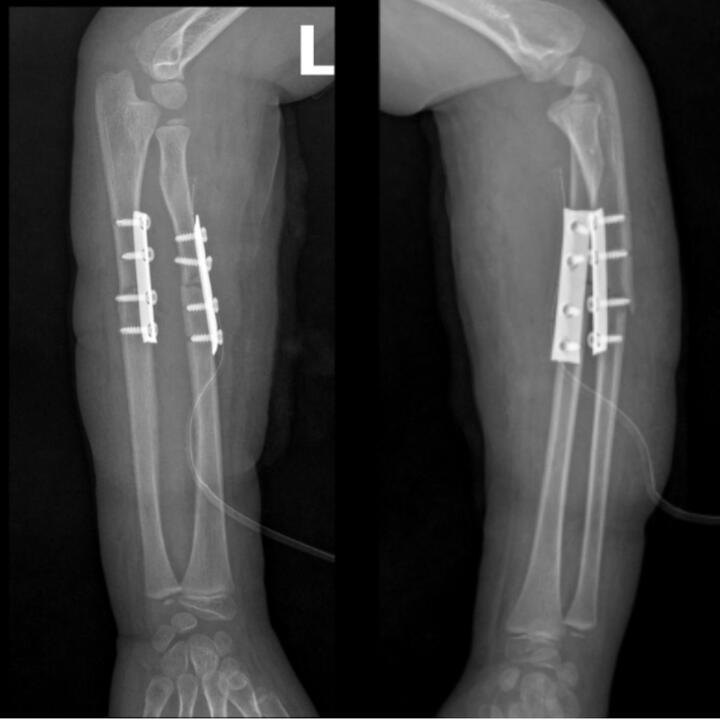

Sau hơn 1 giờ phẫu thuật, dưới sự hỗ trợ của hệ thống máy C-arm, ê-kíp phẫu thuật tiến hành nắn chỉnh trục xương giúp đưa hai đầu xương gãy và mảnh xương di lệch về đúng vị trí giải phẫu, khôi phục chiều dài và chức năng sấp, ngửa của cẳng tay. Sau đó, phẫu thuật viên đặt nẹp vít cố định nhằm giữ vững hai đoạn xương, tạo điều kiện cho quá trình liền xương diễn ra đúng vị trí giải phẫu, tránh nguy cơ sai lệch hoặc biến dạng.

Toàn bộ quá trình phẫu thuật được thực hiện qua một đường mổ nhỏ ở phía trước. Chỉ với một đường tiếp cận này, phẫu thuật viên có thể nắn chỉnh và cố định đồng thời cả hai xương gãy, giúp giảm tổn thương phần mềm, hạn chế mất máu và giảm đau sau mổ cho bệnh nhi.

Phẫu thuật kết hợp xương cố định xương gãy, phục hồi vận động sớm.